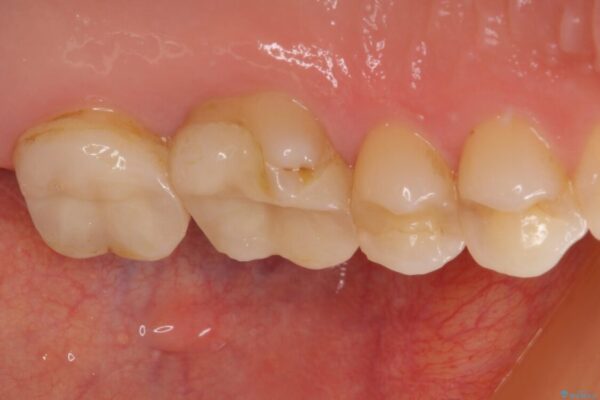

奥歯がズキズキと痛み、食事で噛むことができないとのことで来院された患者様です。 以前治療を受けたとき、むし歯が大きかったため、神経組織が炎症を起こす可能性があると指摘をされていたとのことでした。

治療前

• 奥歯がズキズキと痛む 奥歯の虫歯治療 治療前画像